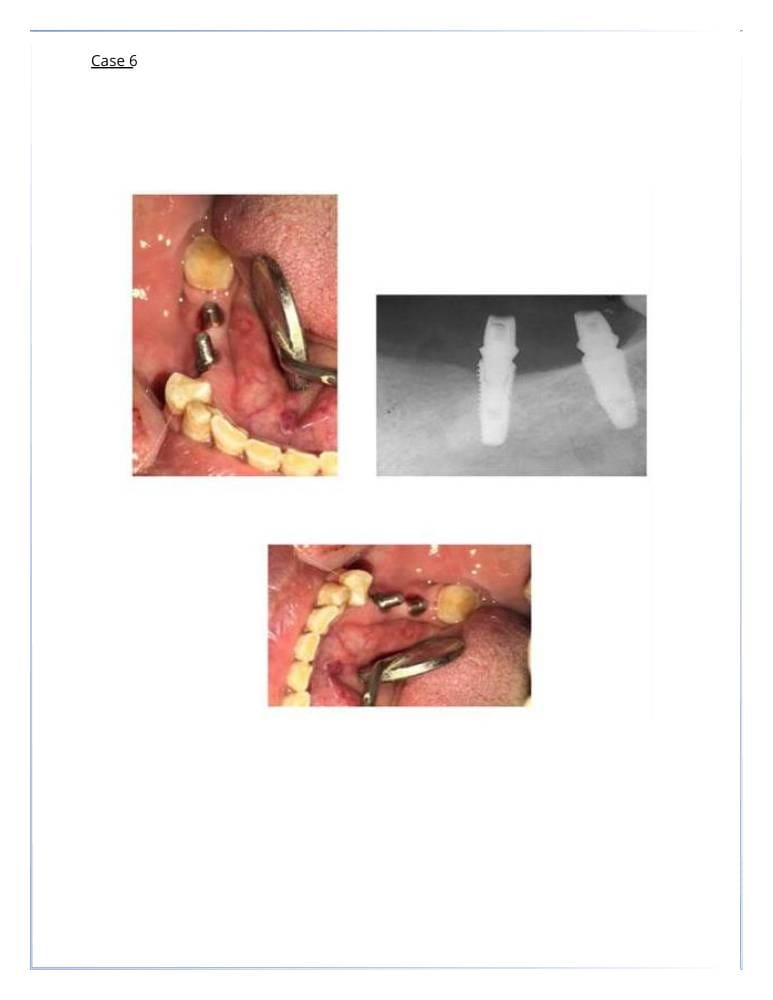

زراعة الأسنان

- استبدال الأسنان المفقودة بزراعات دائمة.

- توفير الدعم للتركيبات المتحركة أو الثابتة.

- خلع الاسنان والزراعه في نفس الجلسة.